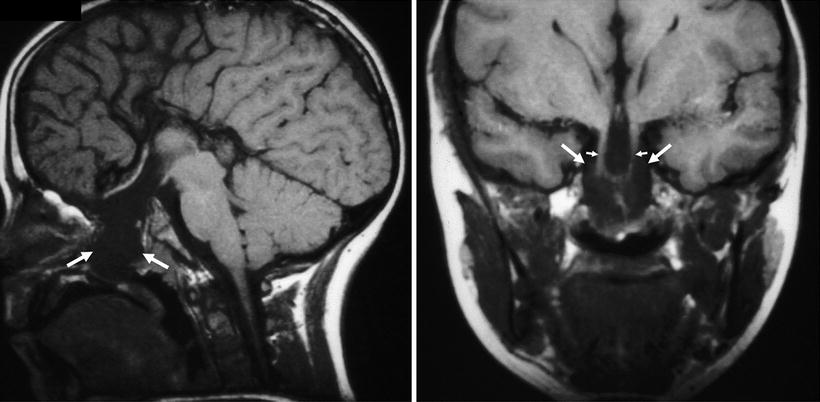

Neurohypophyseal Abnormalities

Posterior pituitary ectopia. (a) T1-weighted sagittal MR image demonstrating normal hyperintense signal of posterior pituitary gland (lower white arrow), normal pituitary infundibulum (lower white arrow), optic chiasm (upper white arrow). Open arrow denotes normal corpus callosum. (b) T1-weighted sagittal MR image demonstrating posterior pituitary ectopia (upper white arrow), which appears as abnormal focal area of increased signal intensity at tuber cinereum. Note absence of pituitary infundibulum and absence of normal posterior pituitary bright spot (lower white arrow). Upper white arrow denotes ectopic posterior pituitary gland. This child had a normal septum pellucidum and corpus callosum. Used with permission, from Brodsky and Glasier [58]. Copyright 1993, American Medical Association.

The finding of an absent pituitary infundibulum with no orthotopic or heterotopic bright spot corresponding to the posterior pituitary gland (Fig. 11.42) signifies loss of antidiuretic hormone secretion, which is associated with diabetes insipidus. When this finding is present, the anterior pituitary hormones are deficient as well.